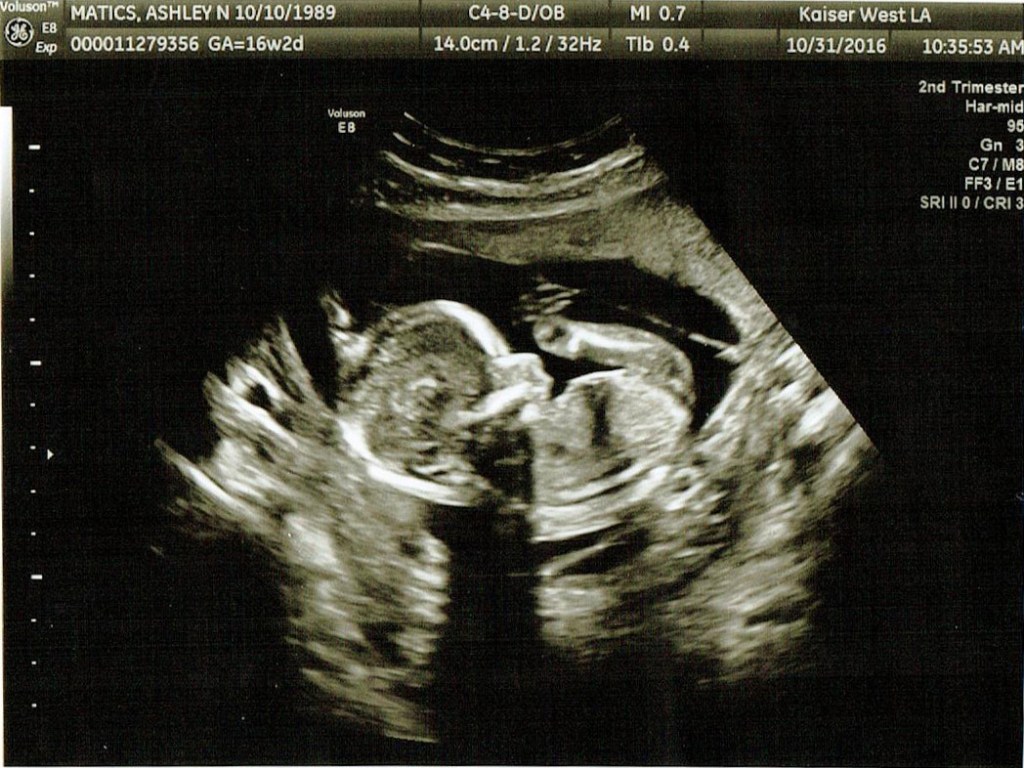

Here are this weeks ultrasound pictures:

We found out the sexes on October 24th, and if you look carefully at the photo that brought you to this post you should be able to find out too!